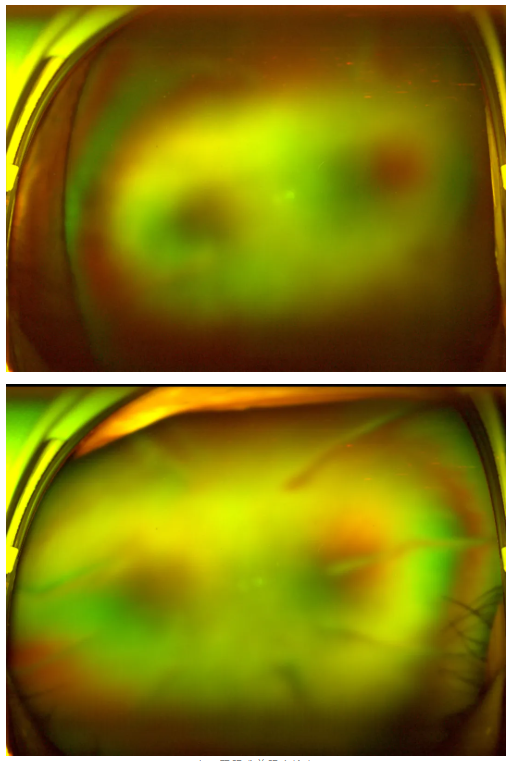

糖尿病視網(wǎng)膜病變

老王雙眼術(shù)前眼底檢查

王曉波主任告知老王:術(shù)后復(fù)查眼底顯示,其糖尿病視網(wǎng)膜病變并不嚴(yán)重,因此視力得以得到明顯改善與提升。當(dāng)初堅(jiān)持治療、不輕言放棄,是非常正確的選擇!